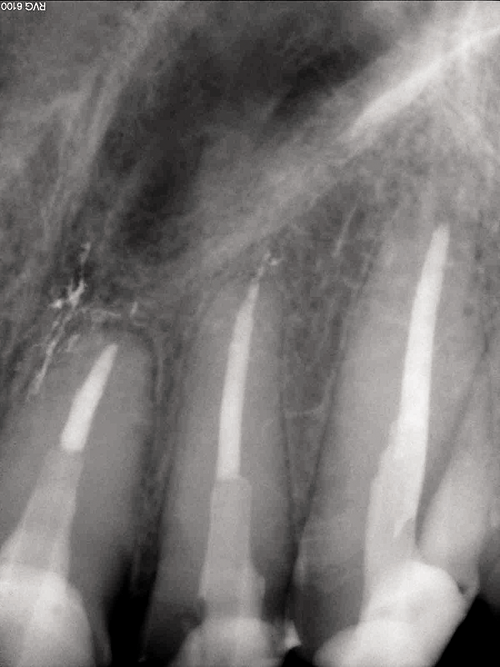

He also had numerous areas of new decay in most of his remaining teeth, requiring a full mouth reconstruction. Our treatment plan was a 24 tooth reconstruction (missing first bicuspids) with root canal treatment for teeth #7-11 with fiber post build-ups using CORE-FLO DC LITE.

On the maxillary preparation day the entire upper arch was anesthetized with articaine with 1:100,000 epinephrine and a full arch rubber dam placed (Fig. 4). The severely damaged anterior teeth #7-11 were cleaned and shaped for gutta percha final fill, then prepared for the fiber core posts (Fig. 5). Bisco’s dual-cured UNIVERSAL PRIMER was placed and agitated for 30 seconds on all five teeth at once.

After thorough drying with air and paper points, the CORE-FLO DC LITE was injected into the canals one at a time with the fiber core posts immediately inserted. Each tooth was shaped and built up by adding CORE-FLO DC LITE as needed (Fig. 2, 6).